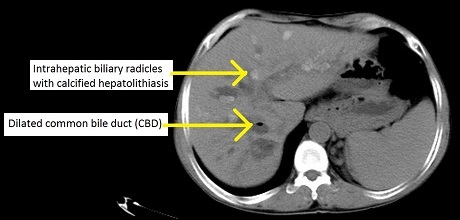

과거에는 주로 내시경 역행 쓸개이자조영(ERCP)을 통해 담관을 촬영했다. ERCP에서는 간 안팎의 담관이 염주 모양(좁아짐과 넓어짐이 반복되는 형태)으로 보이는 특징적인 소견이 나타난다. 그러나 ERCP는 침습적인 검사이다. 현재는 비침습적이면서도 정확도가 높은 자기 공명 쓸개이자조영(MRCP)이 진단적 담관 조영술에 선호되는 방법이다. MRCP는 자기 공명 영상(MRI) 기술을 이용하며, 공간 해상도가 높아 미세한 담관 구조까지 시각화할 수 있다.[21] 복부 초음파 검사나 컴퓨터 단층 촬영(CT)도 보조적으로 사용될 수 있다.

CT 스캔으로 확인한 원발 경화 쓸개관염 사례

총담관의 초음파 영상